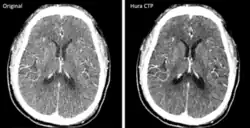

Original (left side) compared to reconstructed (right side) brain image produced from CT scans with low radiation dose. Reconstruction method improves image quality for accurate diagnosis.

The development and FDA clearance of photon-counting detectors (PCD) for computed tomography (CT) scans in 2022 was an important innovation. These detectors offer a more efficient process for converting X-rays to electrical signals, allowing for better material differentiation and potentially reducing the radiation dose for patients. The image to the right shows two scans of the same brain using old and new CT technology respectively.[24]